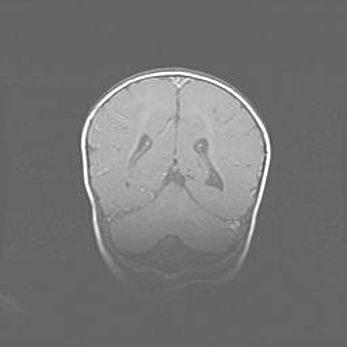

Открытая гидроцефалия.

Возраст: 9 месяцев 12 дней

Вес: 6800 г

Пол: мужской

Окружность головы: 41,5 см

Срок гестации: 28 недель

Гидроцефалия головного мозга у новорожденных имеет характерный признак: опережающий рост окружности головы приводит к визуально хорошо определяемой гидроцефальной форме сильно увеличенного в объёме черепа. Детские неврологи определяют следующие симптомы гидроцефалии у грудничков: выбухающий напряжённый родничок, частое запрокидывание головы, смещение глазных яблок к низу.